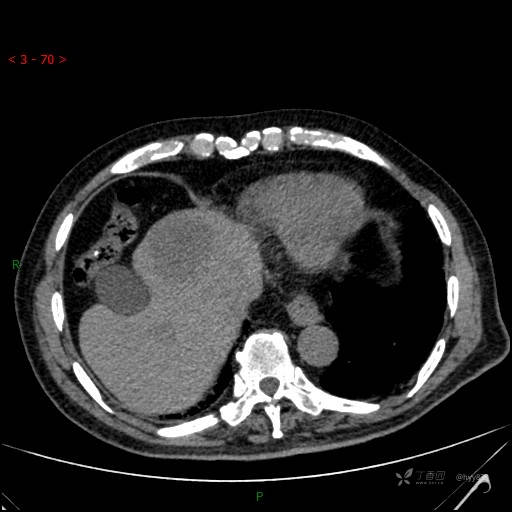

肝脏CT平扫

img